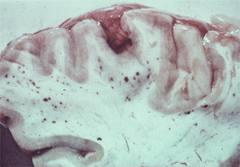

Tăng áp lực sọ não là một đặc điểm của sốt rét ác tính ở trẻ em đang sống tại châu Phi. Nhóm nghiên cứu đã điều tra về hình ảnh đĩa thị trên lâm sàng của phù gai thị (clinical optic disc features of papilledema) để thiết lập ý nghĩa tiên lượng của họ về bệnh lý não trong trường hợp này. Họ đã phát triển một bảng phân loại của phù gai thị cấp và thử nghiệm chống lại bệnh thông qua can thiệp. Các trẻ em Kenya nhập viện vì sốt rét ác tính (có biểu hiện hôn mê hoặc rối loạn ý thức) soi đáy mắt dãn thông qua sử dụng một phương pháp soi mắt trực tiếp và gián tiếp. Các đặc điểm lâm sàng của đĩa thị được ghi nhận một cách hệ thống và bài bản và so sánh với hậu quả trên trẻ.Các kết quả được xác định như là tử vong hoặc suy giảm thần kinh vào lúc ra viện được dùng để xây dựng và kiểm tra phân loại lâm sàng cho phù gai thị (papilledema). 45 trẻ được kiêm tra (26 ca SRATTN, 17 ca SRAT có rối loạn ý thức và tình trạng kiệt sức) trong số đó có 7 trẻ hậu quả kém (3 ca tử vong, 4 ca có di chứng suy sụp thần kinh tồn tại). Mất hình ảnh ly đĩa thị (optic disc cup) và đánh giá đĩa thị có liên quan ý nghĩa với tiên lượng xấu (P < 0.05). Độ trầm trọng của bệnh gia tăng trong phân loại đề nghị này của phù gai thị cấp là tương ứng với hậu quả xấu(P < 0.05).

Thiếu các hình ảnh đĩa thị hình chén và tăng đáng kể của của đầu đĩa thị dường như có liên quan đến tiên lượng xấu trên trẻ em bị SRAT, ngược lại sự có mặt của của các tĩnh mạch dãn cho thấy tiên lượng tốt. Bảng phân loại được đề nghị của phù gai thị cấp có ích như một chỉ điểm tiên lượng (prognostic indicator) và có thể áp dụng cho các bệnh lý não khác có gia tăng áp lực sọ não.